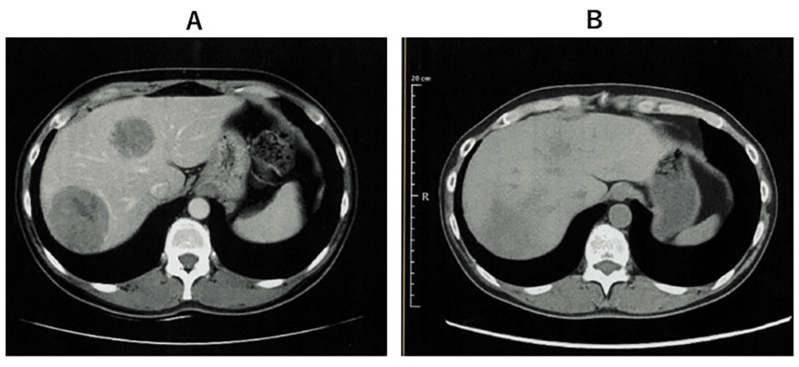

案例2:难治性宫颈癌转移灶消失,免疫功能恢复